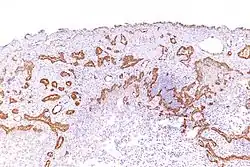

Micrograph of a malignant epithelioid mesothelioma stained with an antibody against calretinin

Using immunohistochemistry, calretinin can be demonstrated in both benign mesothelium and in malignant mesothelioma[12][13] and can be used to help differentiate different lung tumours.[14] Antibodies to calretinin can also be used to distinguish between different types of brain tumour, demonstrating only those with neuronal rather than glial, differentiation.[15] Furthermore, the essential function of calretinin in mesothelioma cell lines has been demonstrated in vitro and may be an interesting target for therapeutical approaches.[16]